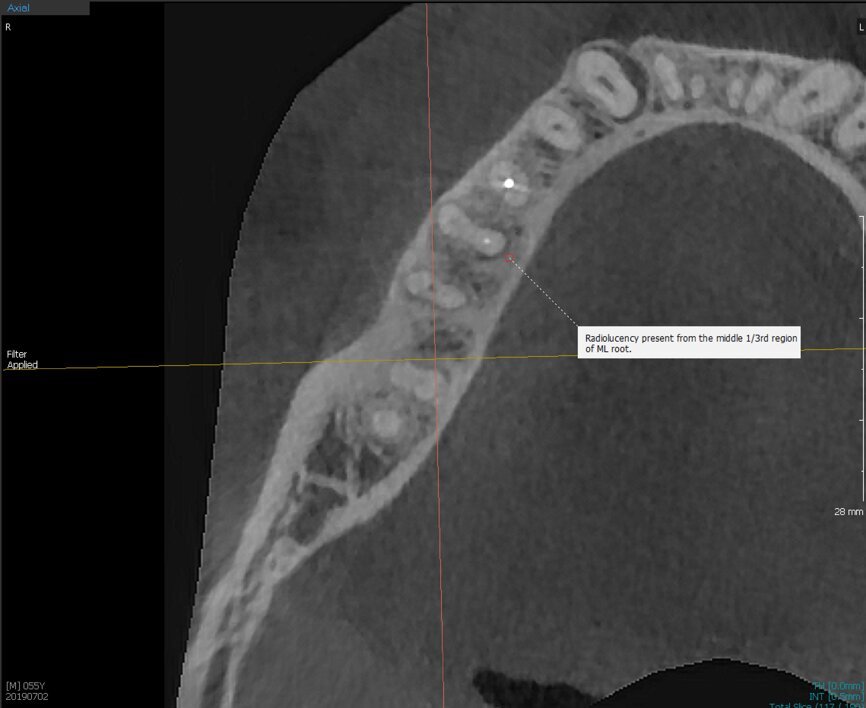

Fig.2a: Pre-op CBCT images of tooth #46: No obturation material in the distal and mesiobuccal canal (a); scanty obturation of the canals and breach of the floor of the pulp chamber, no obturation beyond a few millimetres down the orifice (b & c); radiolucency in the furcation area and periapical region of both roots (d -g).

Fig.2b: Pre-op CBCT images of tooth #46: No obturation material in the distal and mesiobuccal canal (a); scanty obturation of the canals and breach of the floor of the pulp chamber, no obturation beyond a few millimetres down the orifice (b & c); radiolucency in the furcation area and periapical region of both roots (d -g).

Fig.2c: Pre-op CBCT images of tooth #46: No obturation material in the distal and mesiobuccal canal (a); scanty obturation of the canals and breach of the floor of the pulp chamber, no obturation beyond a few millimetres down the orifice (b & c); radiolucency in the furcation area and periapical region of both roots (d -g).

Fig.2d: Pre-op CBCT images of tooth #46: No obturation material in the distal and mesiobuccal canal (a); scanty obturation of the canals and breach of the floor of the pulp chamber, no obturation beyond a few millimetres down the orifice (b & c); radiolucency in the furcation area and periapical region of both roots (d -g).

Fig.2e: Pre-op CBCT images of tooth #46: No obturation material in the distal and mesiobuccal canal (a); scanty obturation of the canals and breach of the floor of the pulp chamber, no obturation beyond a few millimetres down the orifice (b & c); radiolucency in the furcation area and periapical region of both roots (d -g).

Fig.2f: Pre-op CBCT images of tooth #46: No obturation material in the distal and mesiobuccal canal (a); scanty obturation of the canals and breach of the floor of the pulp chamber, no obturation beyond a few millimetres down the orifice (b & c); radiolucency in the furcation area and periapical region of both roots (d -g).

Fig.2g: Pre-op CBCT images of tooth #46: No obturation material in the distal and mesiobuccal canal (a); scanty obturation of the canals and breach of the floor of the pulp chamber, no obturation beyond a few millimetres down the orifice (b & c); radiolucency in the furcation area and periapical region of both roots (d -g).

When I had a close look at the preoperative radiograph from the referring dentist (Fig. 1a), I observed that there was insufficient obturation of the mesial canals and almost no obturation of the distal canal. Both roots displayed periapical radiolucency. The clinical examination revealed a Grade I mobility, and the tooth was tender to percussion. The periodontal examination ruled out any pockets and loss of attachment. We took an intra-oral periapical radiograph (Fig. 1b), from which we observed the loss of coronal structure and a large radiolucent area over the furcation area and the periapical area of both the mesial and the distal roots. A CBCT scan of tooth #46 was advised to check for any details that may have been missed in the intra-oral periapical radiograph (Figs. 2a–g). From the CBCT scan, it could be observed that there was inadequate obturation of the distal canal on the horizontal plane, no obturation beyond the middle third in the mesial canals and a breach of the floor of the pulp chamber. The questionable prognosis was explainedto the patient, and written consent was obtained.